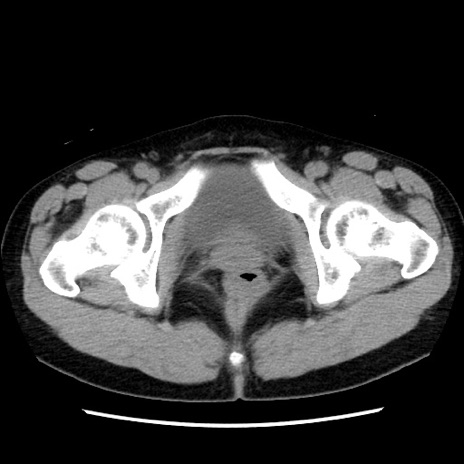

症例10(横断像)

【症例】 50歳代女性

【主訴】 腹痛

【現病歴】前日生レバーを食べた。今朝に排便あり。 昼前に突然発症の腹痛を生じ、当院救急外来を受診した。

【既往歴】 子宮筋腫にてで子宮全摘後

【身体所見】 意識清明、腹部:平坦、軟、下腹部やや左を中心に圧痛・反跳痛あり、筋性防御あり

【データ】WBC 7800、CRP 0.07